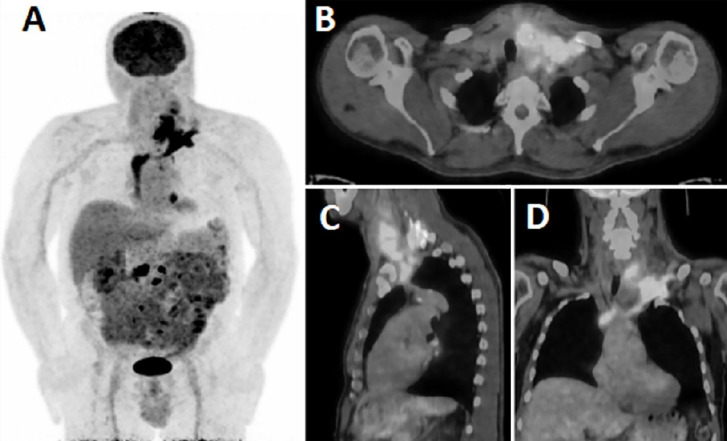

一名59岁男子入院,主诉左臂和颈部疼痛。对可能出现的颈椎脱臼进行磁共振成像检查。C7椎体可见病变伴周围骨髓水肿,与颈椎狭窄的转移相吻合。行颈椎狭窄手术,病理诊断为甲状腺癌转移灶。18f -氟脱氧葡萄糖正电子发射断层扫描/计算机断层扫描(18F-FDG PET/CT)进行进一步评估。PET/CT图像显示左颈内静脉至右心房的18F-FDG摄取增加。它被认为是恶性血栓。

A 59-year-old man admitted to the hospital complained of left arm and neck pain. Magnetic resonance imaging was performed for possible cervical discopathy. It revealed that in the C7 vertebral body, lesions with surrounding bone marrow edema were observed, which were compatible with metastasis that caused cervical stenosis. Cervical stenosis surgery was performed, and the lesion was pathologically diagnosed as a metastasis of thyroid carcinoma. 18F-fluorodeoxyglucose positron emission tomography/computed tomography (18F-FDG PET/CT) scan was ordered for further evaluation. The PET/CT images showed an increased 18F-FDG uptake from the left internal jugular vein to the right atrium. It was considered a malignant thrombus.